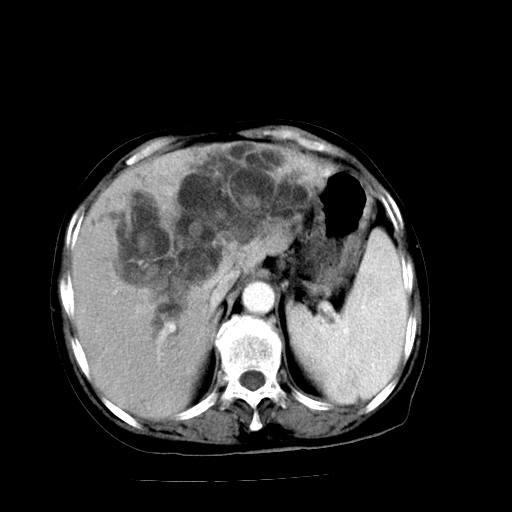

以下是引用卜一在2009-4-7 5:06:00的发言:[br]左右肝内胆管结石伴扩张合并胆系感染;不除外胆管细胞癌可能。支持! [br] [br]

以下是引用随光逐影在2009-4-7 8:21:00的发言:[br]肝内外胆管多发性结石并肝内外胆管扩张;胆系感染。